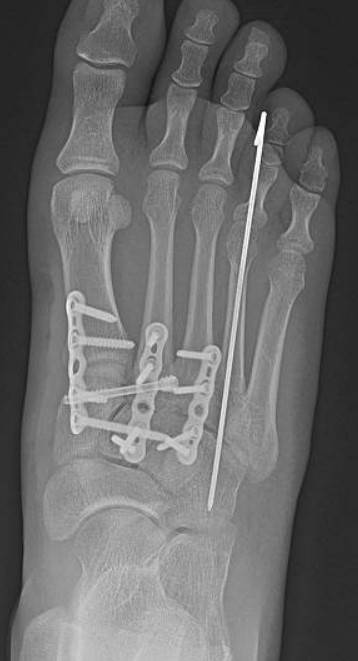

Led by Dr. Vinod Panchbhavi, a world-renowned orthopaedic foot and ankle surgeon, our fellowship covers all aspects of foot and ankle surgery including trauma, reconstruction, ligament and tendon injuries, arthroscopy, arthroplasty, and midfoot and

education. While he practices all aspects of foot and ankle surgery, he has made especially significant contributions in advancing our understanding of charcot arthropathy and Lisfranc injuries.

- Clinical exposure: Between the three attendings, you will have between 500-800 cases for the year, covering all aspects of foot and ankle surgery. Each attending has his own operating style and have different backgrounds so you will be exposed to

a variety of techniques and methods. In addition, UTMB provides medical care to the Texas Department of Criminal Justice, which allows for exposure to some of the most complex pathology possible. Finally, the fellowship is very hands-on and graduated